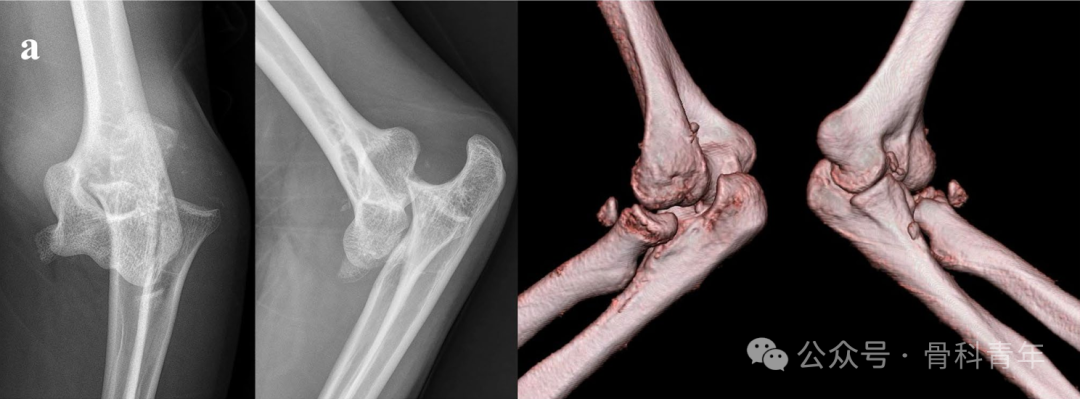

病例2:内侧副韧带止点撕脱骨折合并II型桡骨头骨折,2枚可吸收螺钉固定。